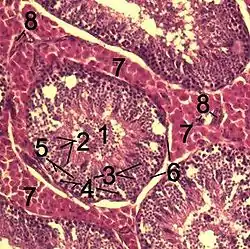

Histological section through testicular parenchyma of a boar.

1. lumen of Tubulus seminiferus contortus

2. spermatids

3. spermatocytes

4. spermatogonia

5. Sertoli cell

6. myofibroblasts

7. Leydig cells

8. capillaries